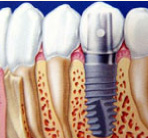

インプラント

第3の歯インプラントも診断が一番大切。適切な治療が成功の鍵です。

入れ歯から開放されて快適な食生活を送って下さい。残っている歯にとっても最適な治療法です。

- イメージ